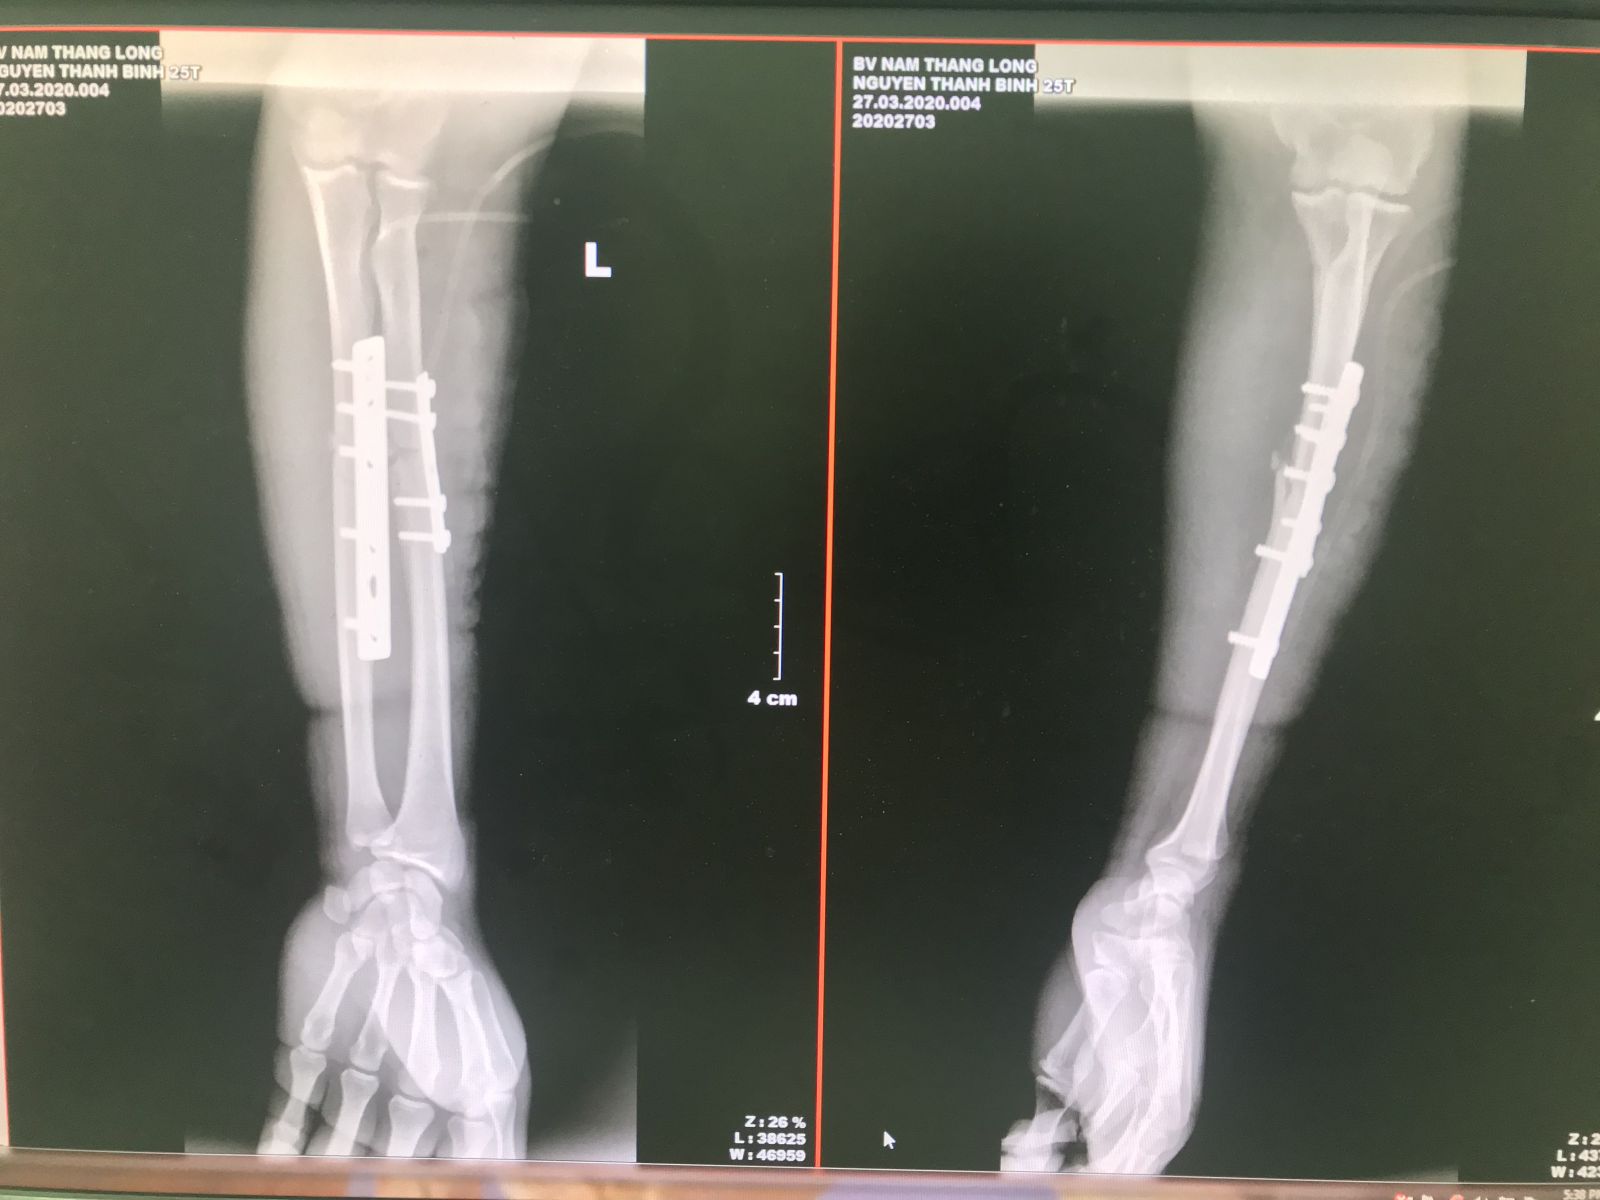

Như trường hợp bệnh nhân N.T.B (25 tuổi) bị tai nạn giao thông, ngã đập cẳng tay trái vào vật cứng, sưng nề biến dạng cẳng tay trái sau tai nạn và được đưa vào Bệnh viện Nam Thăng Long cấp cứu. Bệnh nhân được chẩn đoán: Gãy phức tạp 1/3 giữa 2 xương cẳng tay trái di lệch. Các bác sĩ đã nhanh chóng cấp cứu tích cực cho bệnh nhân cũng như hồi sức dự phòng chống sốc chấn thương, tiêm truyền thuốc giảm đau, dự trù máu, hội chẩn và hoàn thiện xét nghiệm để tiến hành phẫu thuật kết hợp xương bệnh nhân một cách nhanh nhất

Hình ảnh X- Quang 2 xương cẳng tay trước và sau phẫu thuật kết hợp xương

Khoa Chấn thương chỉnh hình bệnh viện Nam Thăng Long hiện đang triển khai phương pháp phẫu thuật kết hợp xương bằng phương pháp sử dụng nẹp vít để cố định xương thẳng trục. Đây là phương pháp ít xâm lấn, phòng ngừa biến chứng cho bệnh nhân gãy xương với nhiều ưu điểm như: Ít tổn thương phần mềm xung quanh, bộc lộ chính xác vị trí ổ gãy xương, giảm thiểu nguy cơ nhiễm trùng, giảm số ngày nằm viện, giảm đau trong mổ và sau mổ tốt, điều kiện tập phục hồi chức năng sớm, bệnh nhân sớm trở lại sinh hoạt bình thường. Với sự đầu tư về nhân lực và máy móc trang thiết bị, bệnh viện Nam Thăng Long là địa chỉ uy tín thực hiện phẫu thuật kết hợp xương hiệu quả với chi phí hợp lý và được thanh toán Bảo hiểm y tế.